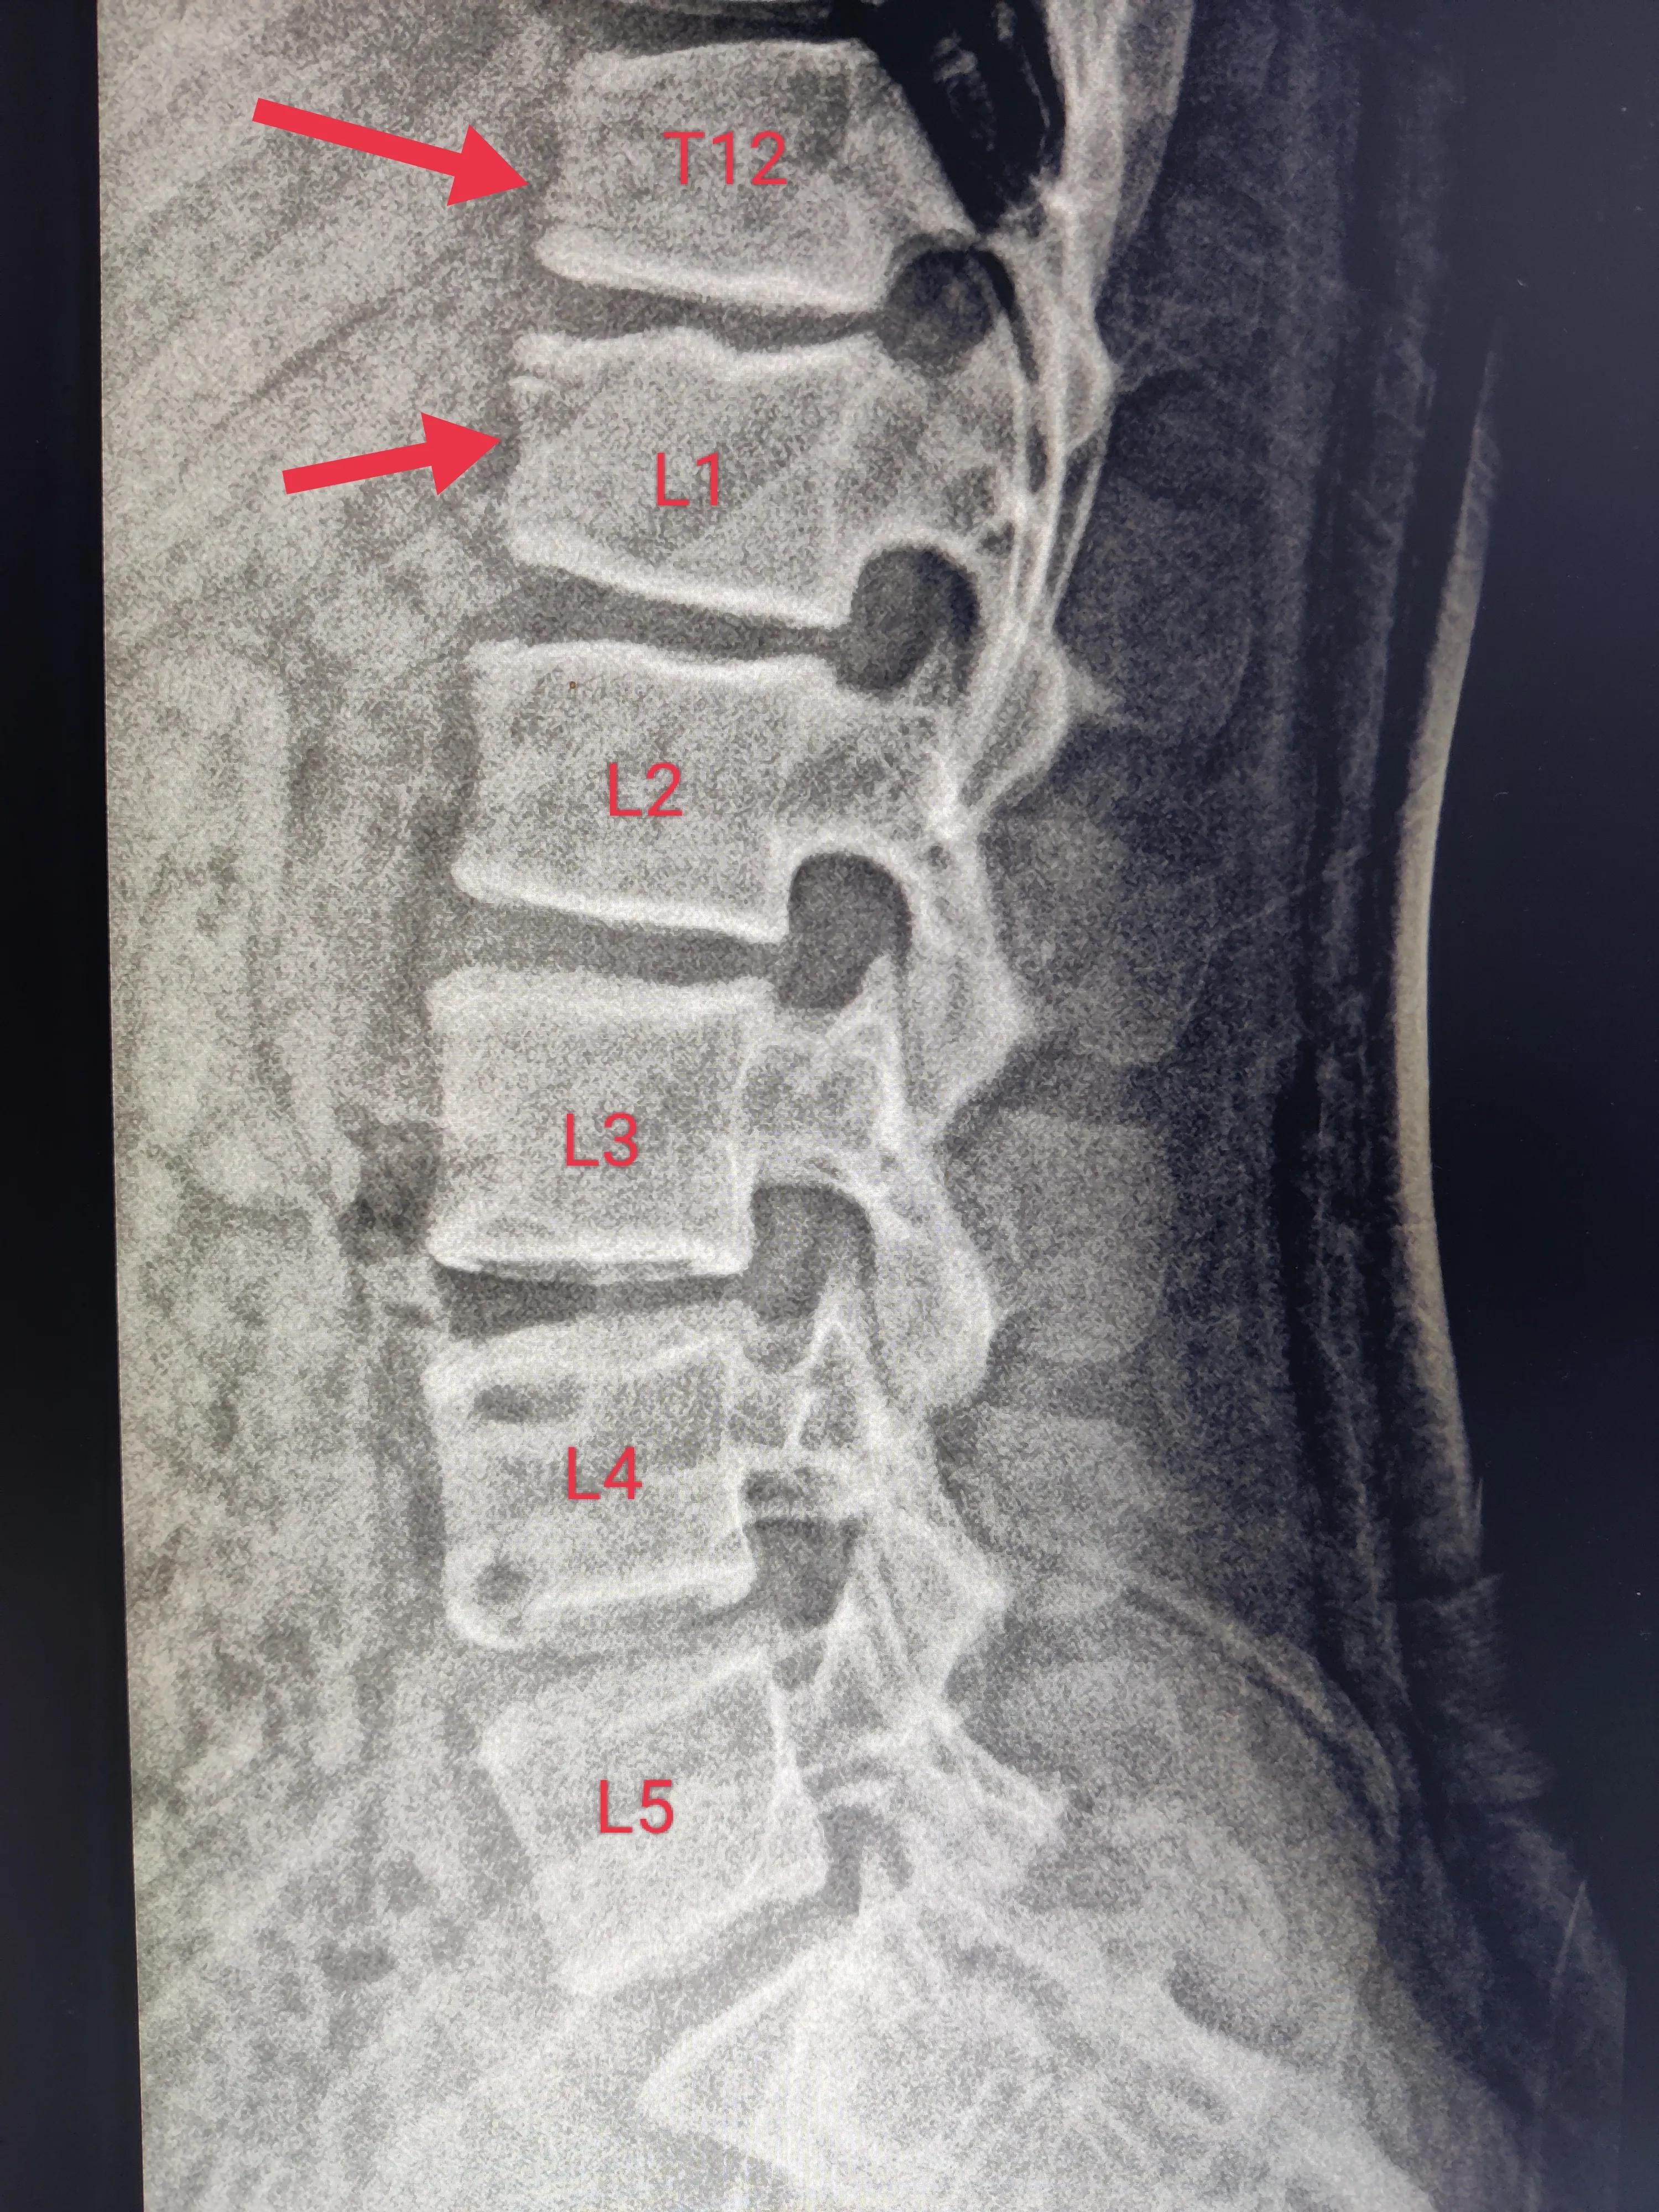

胸12、腰1椎体楔形改变,腰1椎体上缘凹凸不平,胸12-腰2椎体上缘不规整。

之所以叫休门氏病,是因为它是一个叫休门的丹麦医生首先报道的。这种病病因不是很明确,诊断也有一些争议,这个病比较少见,但确是青少年驼背(胸腰椎后凸畸形)伴腰疼的常见的病因。如果不处理,孩子的胸腰椎体楔形改变会越来越多,就会越来越驼背,总会有腰背痛。在这里跟大家解释一下,正常的椎体是近似于方形的,楔形改变就是椎体前面部分变扁了,如果很多椎体都有这种改变,就会出现驼背。当然了,椎体的压缩性骨折,也会有这种楔形改变

腰椎楔形改变